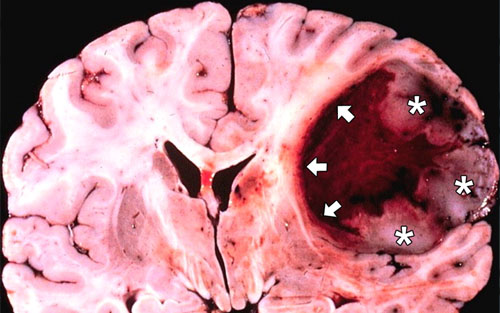

试验并没有大规模地进行,刚开始试验的时候,仅在42个病人身上进行,因为血脑屏障的防护膜会干扰药物预期效果,同时另外其他潜在的风险包括自体免疫反应所引发的,如脑炎、肿胀和恶化等症状也是研究人员考虑的因素之一。吉尔伯特承认“我们必须降低药物试验的速度。”先前有研究表明,免疫疗法能够有效减小患者大脑中的黑色素瘤,这也是免疫疗法的一个令人鼓舞的结果。